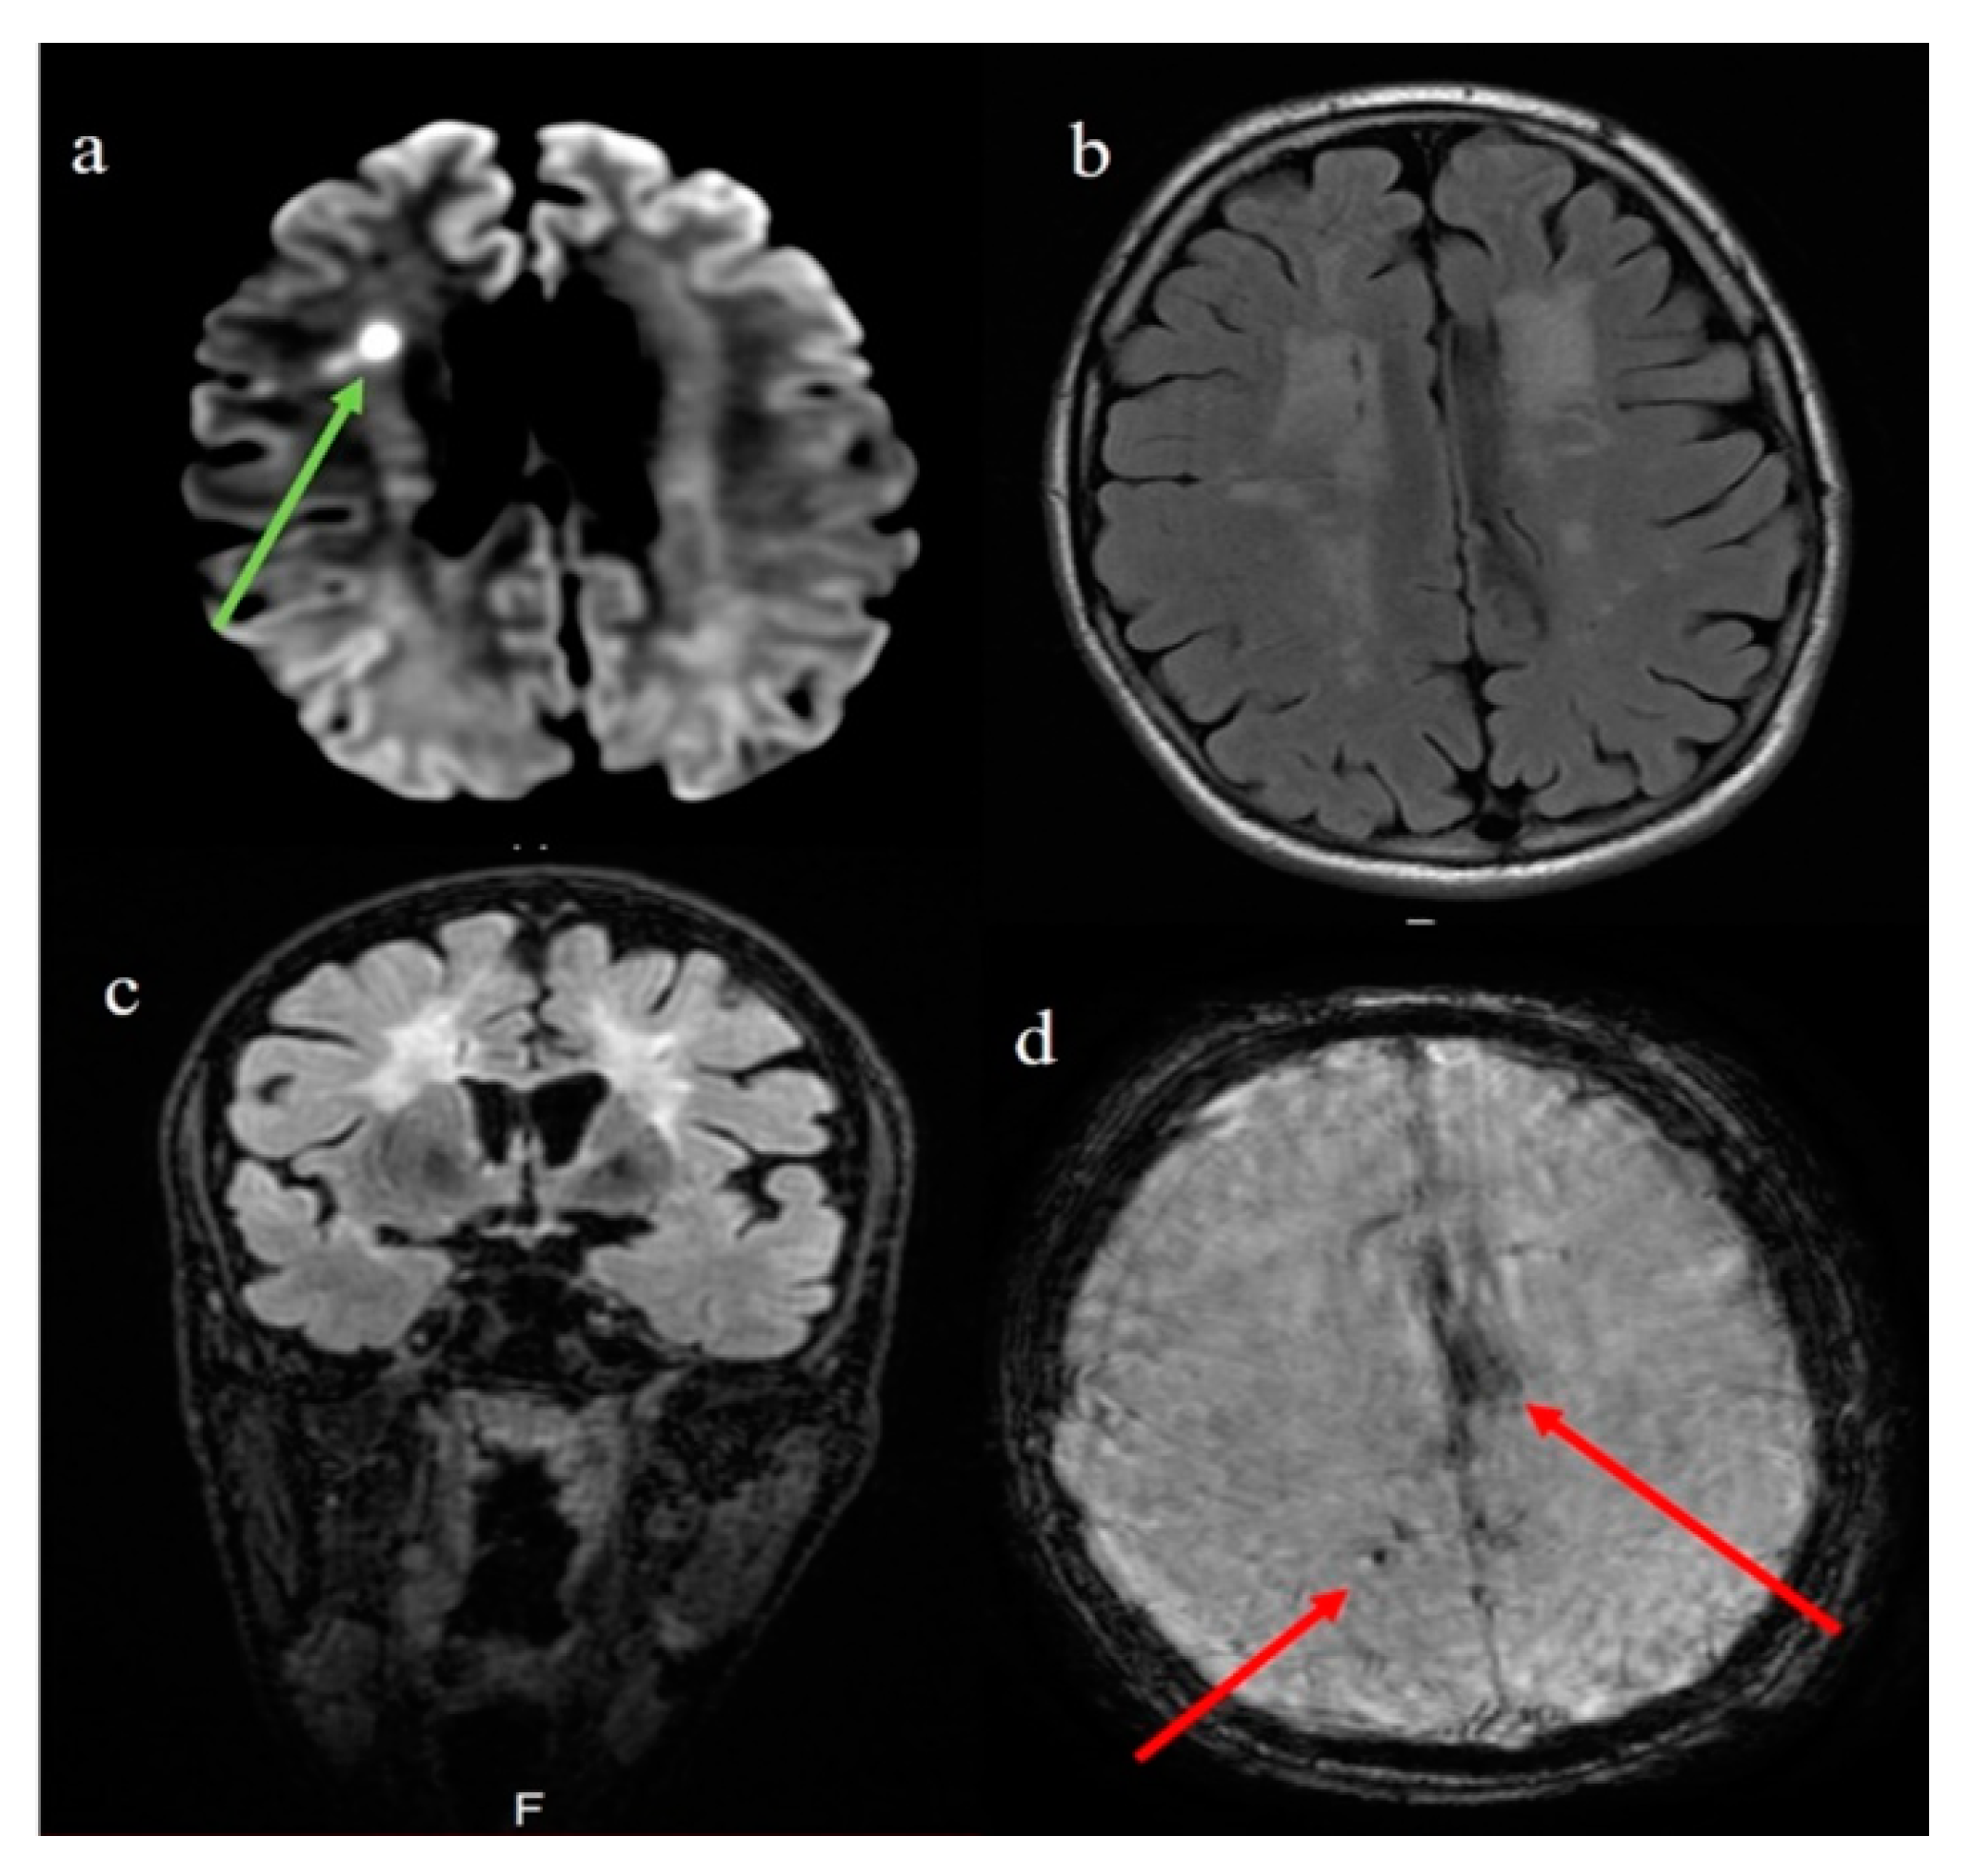

Case Presentation